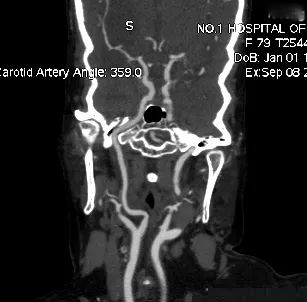

右侧颈内动脉造影显示右侧颈内动脉闭塞。

侧枝代偿差。

术后5月复查CTA显示右侧颈内动脉及大脑中血流通畅。

该病例为颈内动脉C1段远端闭塞,血栓负荷率大,我们采用常规的SWIM技术(支架取栓+抽栓),但是效果不佳,于是改为双支架串联技术取栓,达到mTICI 2b级血管再通效果。

针对本例患者,选择了单纯使用导引导管的双支架串联式释放同时局部并联释放技术,双重支架叠加可以增加支架释放的径向支撑力,同时也增加了支架网丝对血栓的嵌入效应、接触面积和血栓的缠绕能力,快速将血栓拉出体外,提高了开通效率,并最终获得良好开通效果和3个月良好预后。